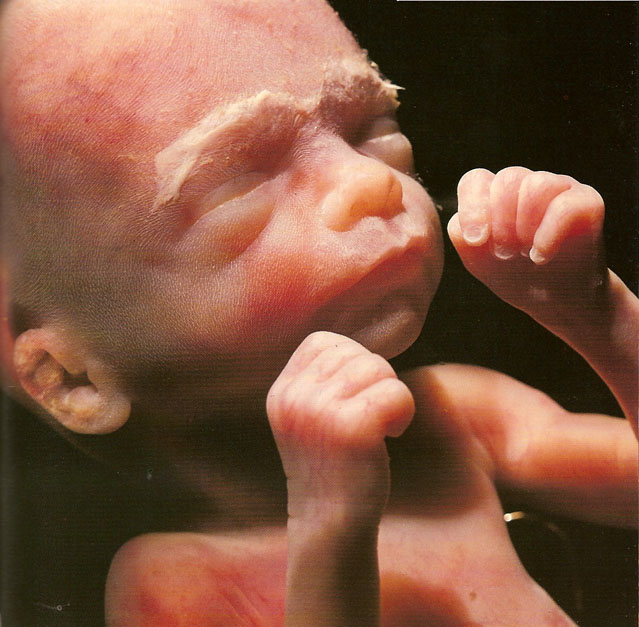

Фото Плода На 21